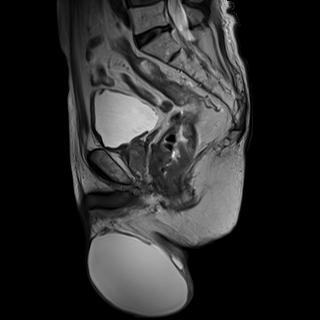

上圖為首發(fā)直腸癌患者,并有睪丸鞘膜積液。